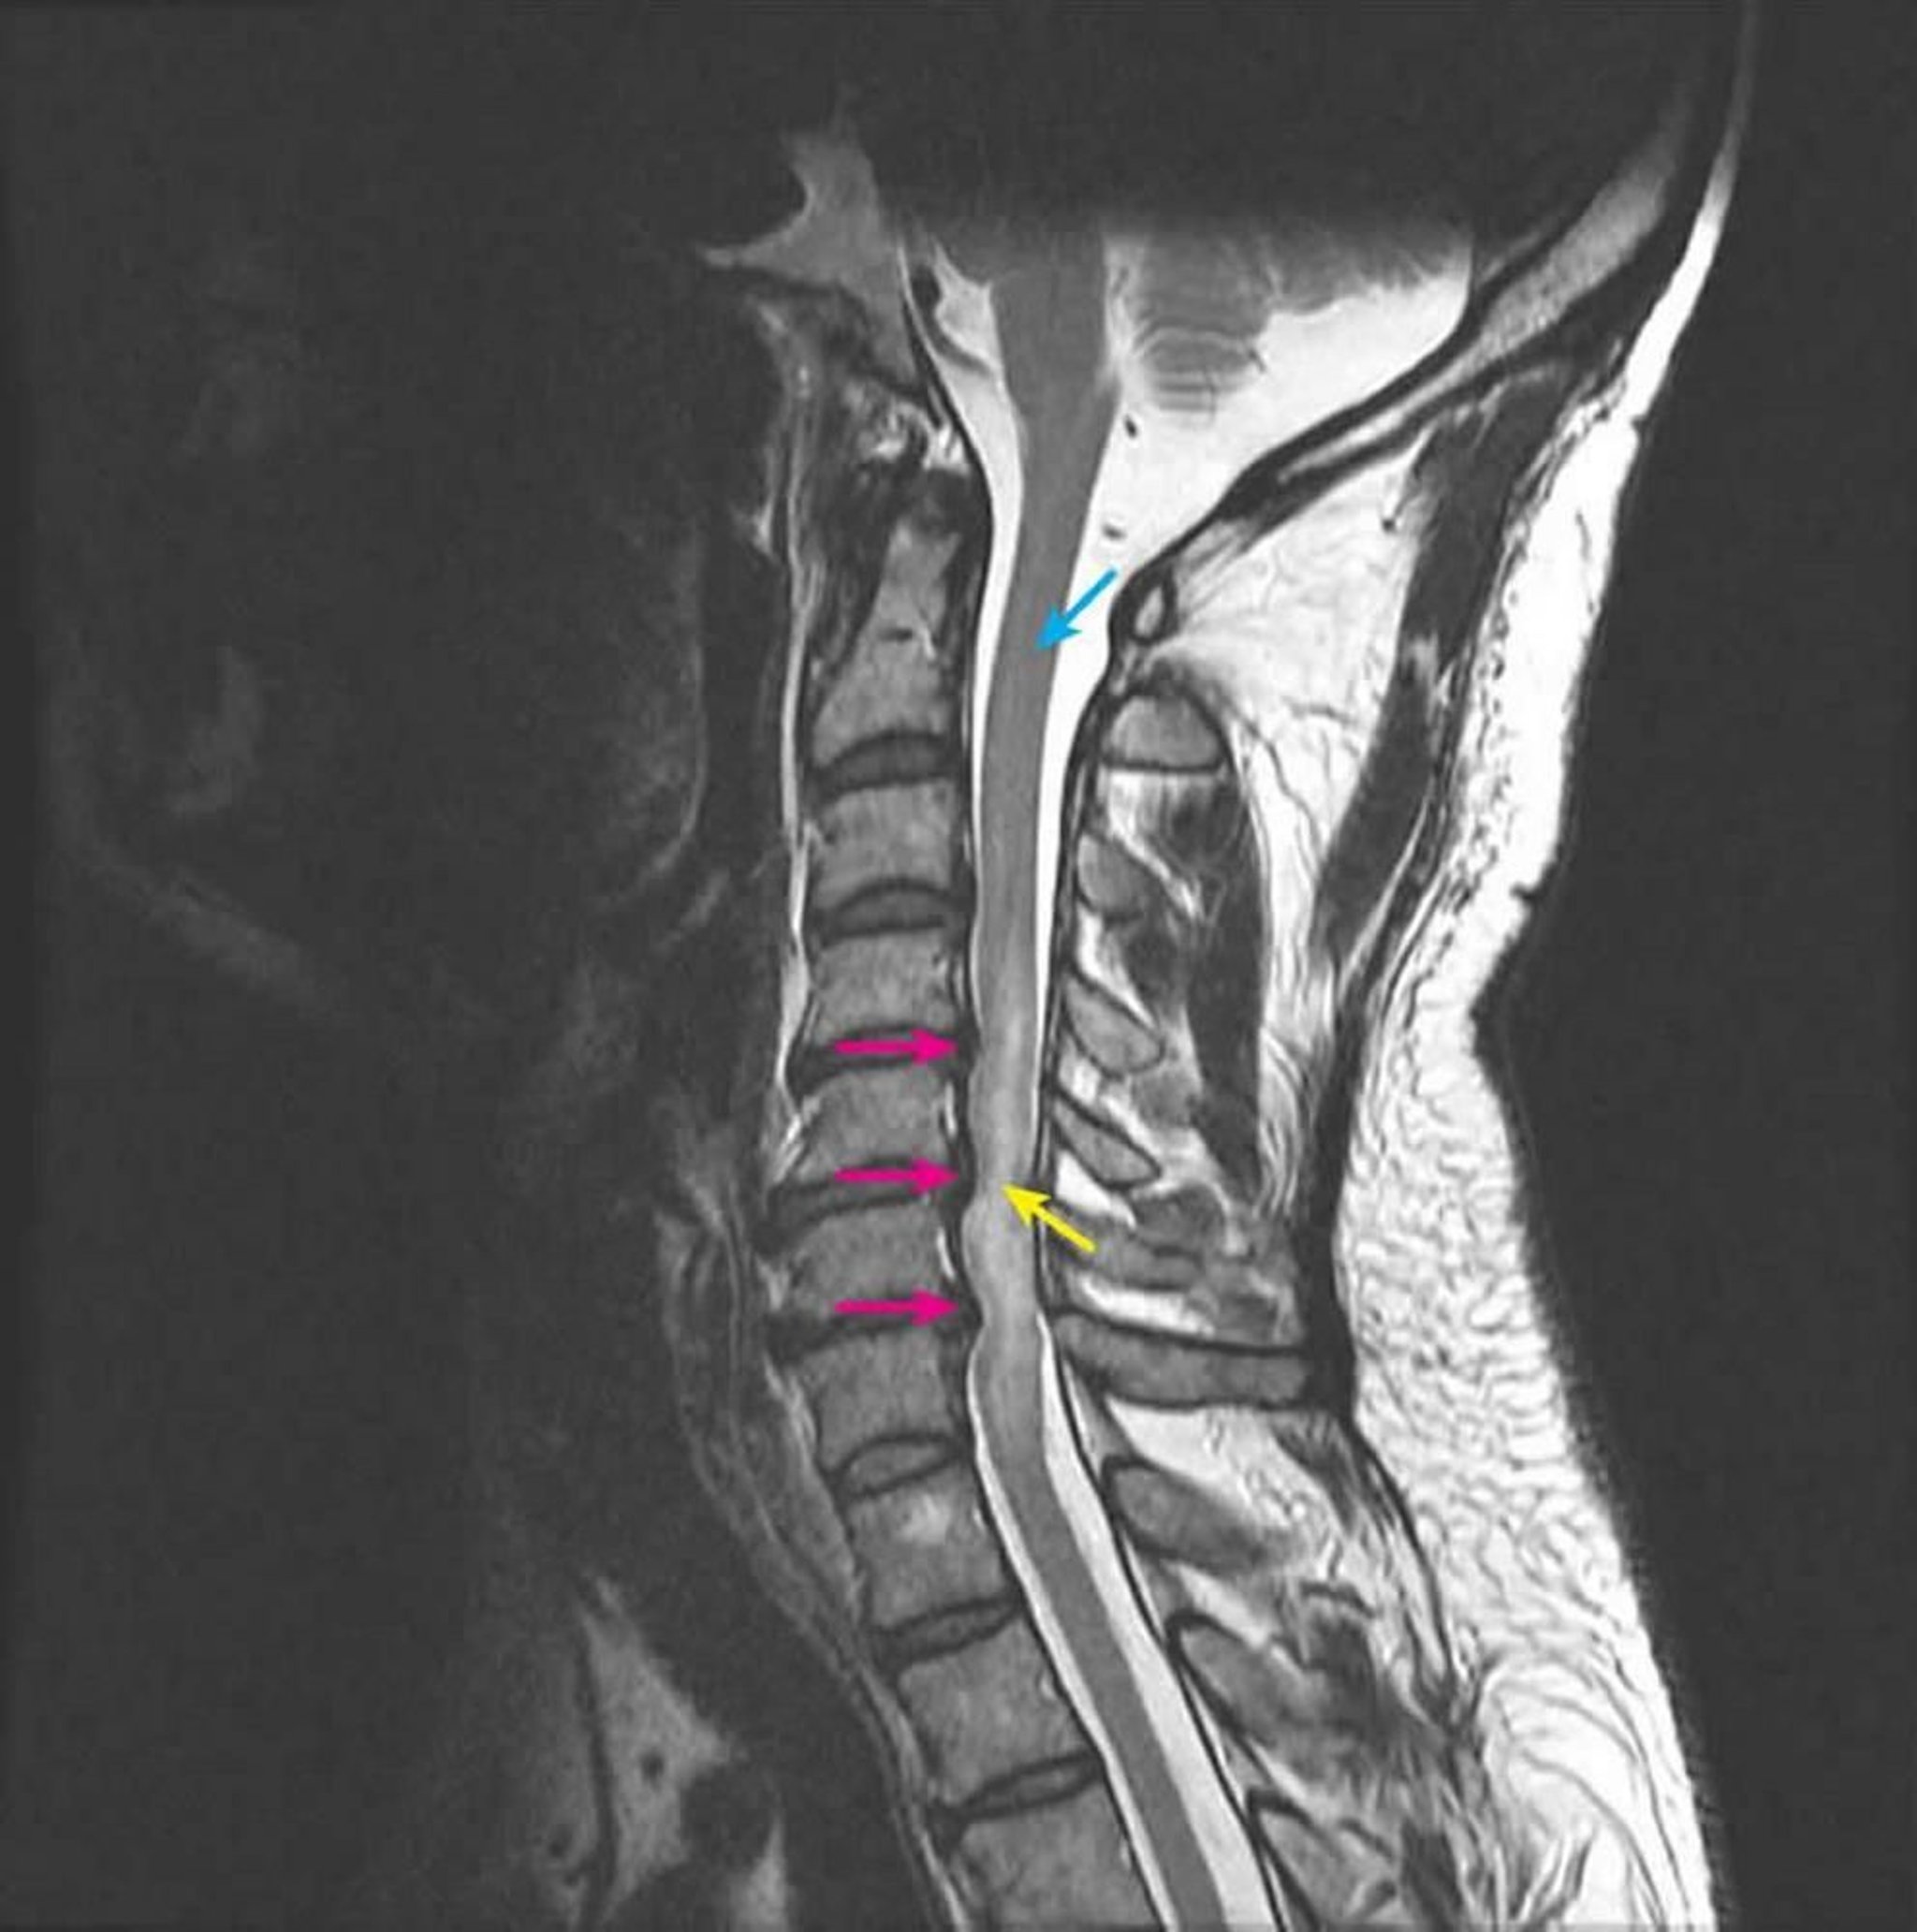

Bệnh lý tủy do chèn ép

Chụp MRI có trọng số T2 theo mặt phẳng đứng cho thấy tình trạng chèn ép tủy sống ở các đốt sống C4-5, C5-6 và C6-7 do thoát vị đĩa đệm sau nhiều mức (mũi tên màu hồng). Tín hiệu T2 trong tủy tăng bất thường, biểu hiện phù tủy sống (mũi tên vàng). Tín hiệu tủy sống bình thường được quan sát thấy ở mức C2 (mũi tên màu xanh).

Được sự cho phép của bác sĩ John Tsiouris, Division of Neuroradiology, New York–Presbyterian Hospital/Weill Cornell Medical Center.